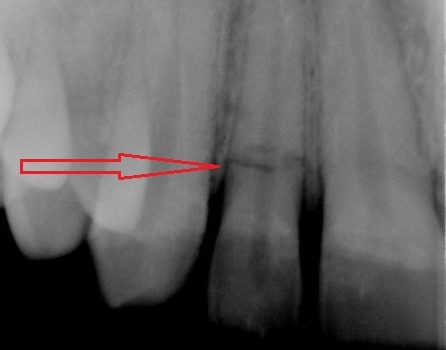

Doğru diaqnostika, müalicə planlaması və sonrakı dönəmdə izləmə uğurlu müalicəyə aparan ən başlıca faktorlardır. Diş travmaları və yaralanmaları tək diş bölgəsini əhatə edən məhdud, eyni zamanda çoxsaylı diş bölgəsini və çənənin alveol darağını əhatə edəcək qədər yayılmış formada rast gəlinə bilir. Çoxsaylı diş zədələnmələrində çox zaman fərqli dişlərdə fərqli növ zədələnmə şəkili aşkar edilə bilir ki, bu da hər bir dişə individual yanaşma və müalicə metodu tələb edir.

Bu tip zədələnmələrin bu sahədə təcrübəsi olan yüksək ixtisaslı həkim tərəfindən həyata keçirilməsi olduqca önəmlidir. Əks təqdirdə yalnış müalicə dişlərin erkən itirilməsinə səbəb ola bilir. Doğru yanaşma ilə isə ciddi zədələnmələrdən sonra belə zədələnmiş dişləri bəzən müəyyən bir müddətə bəzən isə həmişəlik bərpa etmək mümkün olur.